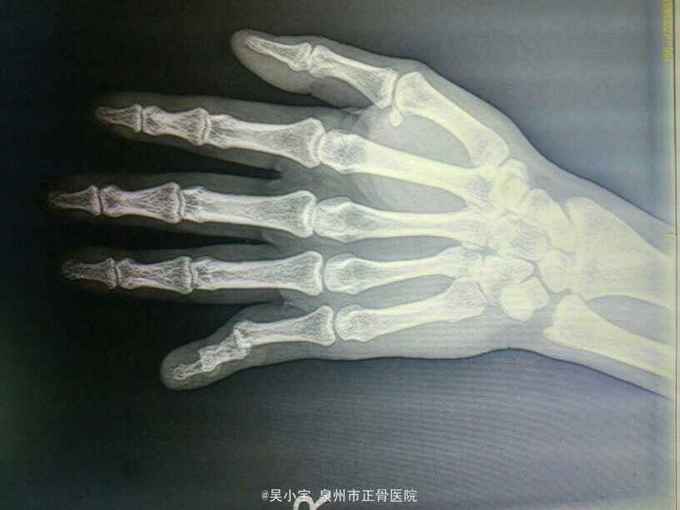

神清,舌淡红,苔薄白,脉弦。心肺腹查体未见明显阳性体征,右手第5手指部成角畸形,未见皮破出血及骨质外露,第5指近、中、远节指骨压痛,未及明显骨擦感及异常活动,左手第5手指活动受限,纵向挤压痛弱阳性,指间关节弹性固定,余各指活动正常,肢端感觉血运好,余肢体关节检查未见明显异常。 辅助检查:右小指正侧位片检查报告(检查号:DR720609,2016.01.06,本院 ) 示:右手第5指近中远节指骨重叠,并向背侧移位,呈脱位状改变;近节指骨远端掌侧缘见一小片状游离高密度影;邻近软组织肿胀。余未见特殊改变。 诊断意见:右手第5指近、远端指间关节脱位,考虑并中节指骨基底部撕脱性骨折。

诊断:1、右手第5指近节、远节指间关节脱位;2、右手第五近节指骨基底部撕脱性骨折。 治疗:手法整复铝板固定, 维持外固定制动,注意肢端感觉及血运情况,如出现肢端麻木、冰冷、变紫、外固定松动或者骨折端疼痛不适,应及时就诊并调整外固定。加强休息,患肢禁活动 2天后门诊复诊,定期复查。